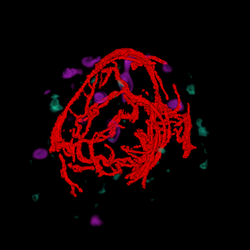

A major task is to implement the abstraction layer for rendering synthetic data, independent of display technology. This may involve use of the MNI's VTk-based IGNS system (IBIS) or build on our own rendering architecture, with low-level rendering engines for each display type, and input taken from existing neuro-visualization tools. In either case, the goal is to integrate the 3D rendering of MRI, fMRI, PET, DTI, and intra-operative ultrasound data, possibly in conjunction with the tracked position of surgical tools, and add modules for additional processing (e.g., feature highlighting, density control, and interactive manipulation/deformation). Rendering strategies must take into account the importance of merging volumetric and surface rendering techniques when dealing with the multiple data sets available.

| cutting plane + MRI | cutting plane + blood vessels | blood vessels + fMRI + PET | blood vessels + fMRI + PET + MRI |

The experimental task was to define a straight vessel-free path from the cortical surface to the targeted tumor using (a pen-like) probe. Because of the complex anatomical structure of the human brain and the topology of key blood vessels, defining such a path for insertion of probes and tools can be a challenging task in practice. For this task, we visualized the segmented brain vasculature with a simulated tumor at positions of varying difficulty of reaching, as shown in Figure a. Subjects were provided with hand-coupled motion cues as they manipulated the volume and probe (Figure b)). Two tangible objects were used as input devices: a small plastic skull to manipulate the orientation and proximity (zoom) of the vasculature, and a replica of a biopsy probe used to locate the tumor. Once the subject was satisfied with the probe position, a foot step, sensed by an electronic game controller dance pad, is used to end the trial. This avoided the risk of introducing jitter to the probe position, which may have resulted otherwise had a manual button press been required.